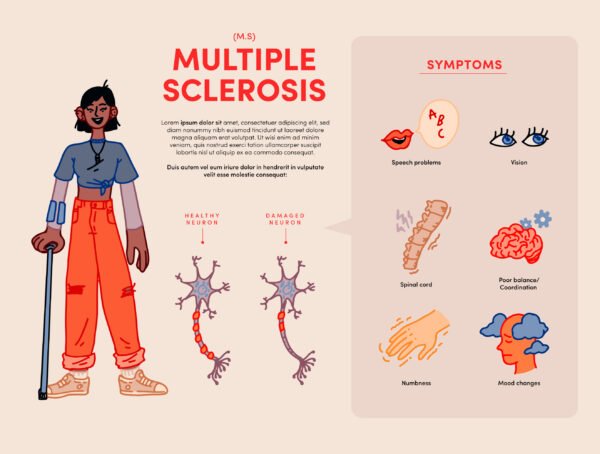

- Multiple Sclerosis